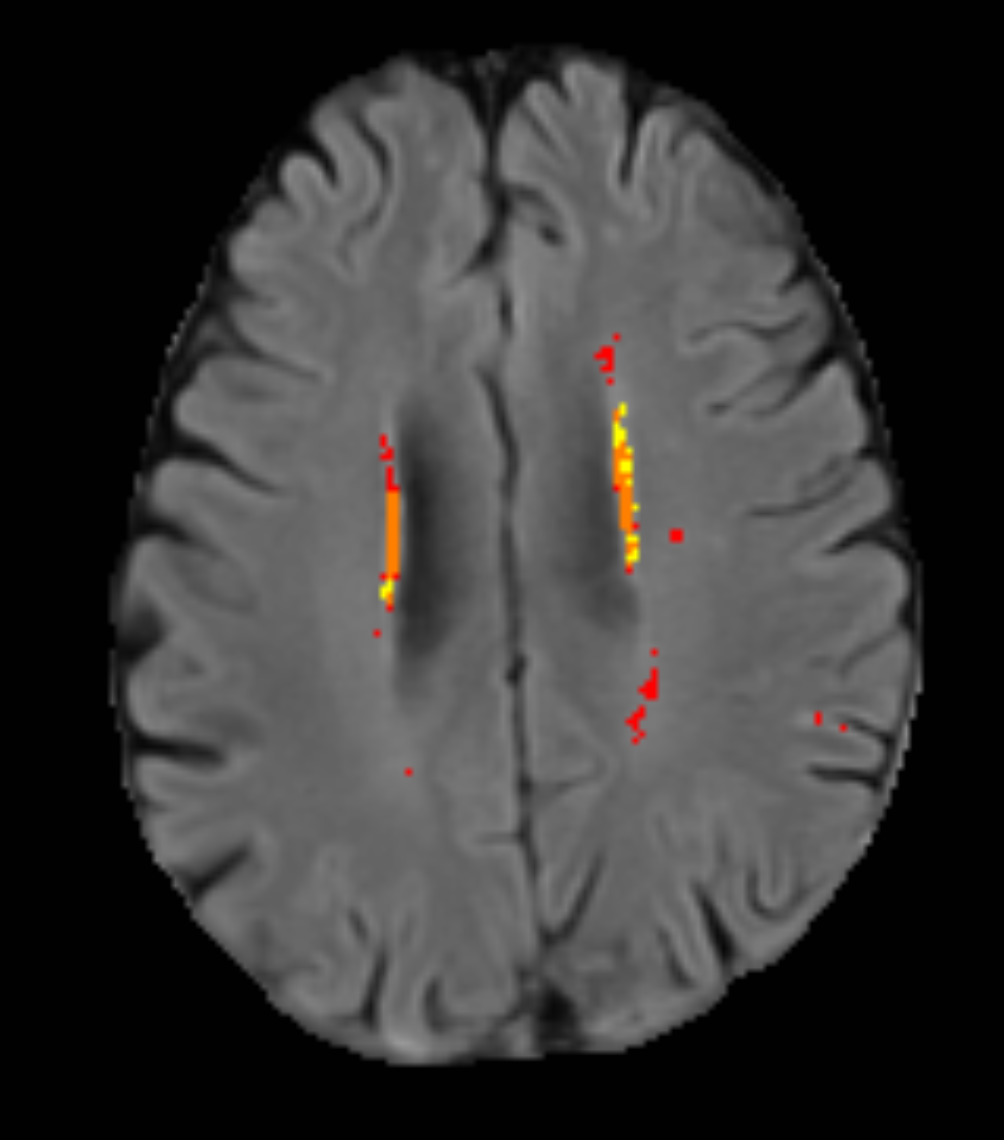

Refer to caption

Figure 2: Test set predictions of the pseudolabels model, grouped into predictions that appear worse, different, or better than the ground truth labels.

We now present qualitative analysis of the pseudolabels model’s output and discuss each prediction shown in Figure 2 in detail.

In Figure 2a we can observe a false positive ISL predicted by the model. This is objectively a bad prediction, since a human expert would not make this error. It is interesting to note that this anatomical feature mistaken for an ISL is relatively symmetrical, but only the right hand side of the image is predicted as an ISL.

Figure 2d shows an ISL that was correctly detected by the model. It is clear to see that the extent of the prediction is significantly less than the extent of the ground truth here. While only about half of the ground truth lesion is hyperintense, the remainder is hypointense and shows clear differences in texture, compared to healthy tissue. Therefore, we would still like the model to be able to segment this area. Because we attempted to filter these types of ISL out of both the training and test sets, it is not surprising that the model has failed here. Interestingly, the model has indeed segmented more than the hyperintense region, but just not the whole lesion

Figure 2b shows an over segmentation of WMH around the anterior horns of the ventricles by the model, relative to the ground truth. Here, the ground truth is simply more conservative regarding the dimmer areas of WMH. The ISL is identified and segmented well. There a slight mismatch between the ground truth and prediction borders, with the prediction being more conservative and appearing only to segment the hyperintense tissue.

Figure 2e shows good agreement between the ground truth and the model prediction for both WMH and ISL (with a slight offset). This example illustrates well a case where two different masks, while not identical, are likely to be of the same clinical utility.

Figure 2c shows a complex case, with a high level of WMH burden. The model segments a greater extent of the periventricular WMH than the ground truth does. It is clear that the ground truth and model are simply following different segmentation policies; the ground truth is more conservative regarding dimmer areas of WMH while the model extends the prediction until the tissue appears normal. This is a subjective choice and it cannot be stated that one mask is correct while the other one is not. The model does however correctly identify several deep WMH instances that are missing from the ground truth. On the left hand side of the image, we can see a correctly identified ISL. Visually, the model appears to better follow the FLAIR-visible borders of the ISL. This highlights an issue that we have made an effort to avoid where information was available to do so; sometimes the ISL ground truth is produced using additional information available in a DWI scan. This is problematic due to the DWI-FLAIR mismatch phenomenon, and even if the mismatch is not significant, often the DWI will be low resolution, resulting in blocky appearing masks when overlaid on the higher resolution FLAIR image. Moreover, sometimes the ground truth is produced at an earlier time point and propagated to the follow-up scan via registration, resulting in border differences due to lesion progression. We cannot expect the model to account for these factors, which is why qualitative analysis is so crucial here. On the right hand side of the image, there are three cavitated hyperintense regions which the model predicts as ISL. When consulted, an expert neuroradiologist suggested that from observing this FLAIR sequence alone, it is plausible that all three of these regions could be ISL.

In Figure 2f we can see another example where the FLAIR-visible border of a cavitated ISL has been well segmented by the model, while the ground truth seems almost incorrect given this FLAIR image alone. It can also be observed that some deep WMH have been correctly identified by the model, which are not segmented in the ground truth.